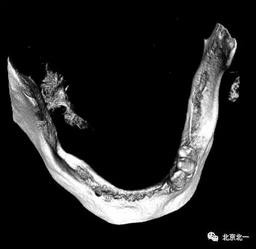

圖七:采用A04技術(shù),拔除下頜余留牙,修整骨平面。在頦孔前方傾斜植入兩枚植體,避開頦孔。減少懸臂。前牙區(qū)植入兩枚直的植體。完成即刻修復(fù)。一日得牙,缺牙后多少年來都沒有吃過蘋果的滋味,到種植牙時(shí)代,想吃什么就吃什么, 我的健康我做主。